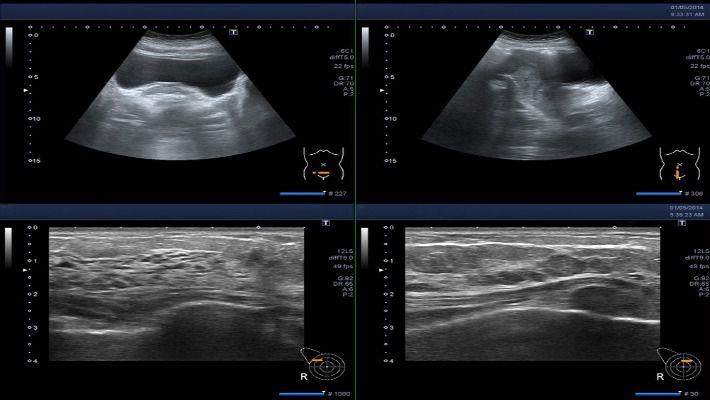

בדיקת סונוהיסטרוסלפינגוגרפיה נחשבת כיום כבדיקת הבחירה הראשונה והמועדפת לאבחון בעיות אי פריון על רקע מכאני. למעשה, מדובר בבדיקת אולטרה סאונד פשוטה המשמשת להדמיית חלל הרחם והחצוצרות. באמצעותה ניתן לבחון את תקינות מבנה הרחם, חלל הרחם והחצוצרות, כדי לוודא שלא קיימת כל חסימה אשר עלולה למנוע כניסה להריון. בניגוד לבדיקת צילום הרחם, בדיקה זו אינה דורשת תפיסה של צוואר הרחם, שימוש בחומר ניגוד (במהלך הבדיקה מוזלפים מים בלבד) וחשיפה לקרינה. על כן, היא נחשבת בטוחה יותר ופחות כואבת מצילום רחם .

במהלך הבדיקה מוזלפת תמיסת מים פיזיולוגיים (סליין) אל תוך הרחם והחצוצרות. בדיקת האולטרה סאונד משמשת כדי להדגים את מעבר הנוזל דרך החצוצרות בזמן אמת ובכדי לבחון את מידת הפתיחה שלהן לשם מעבר נוזלים באופן חופשי וכדי לבחון קיום של ממצאים, כמו פוליפ, שרירן הידבקויות בו. בדיקת הסונוהיסטרוסלפינגוגרפיה אורכת כ-15-10 דקות. לאחר הבדיקה יתכנו תחושת אי נוחות או כאבים הדומים לאלה המורגשים בזמן הוסת החודשית באזור האגן ובבטן. הכאבים נובעים מהתכווצות הרחם. תחושות אלה יחלפו לרוב תוך זמן קצר לאחר הבדיקה. במקרים מסוימים יכול להופיע דימום קל לאחר הבדיקה שמקורו לרוב בצוואר הרחם.

במרכז מור לאישה, בדיקת הסונוהיסטרוסלפינגוגרפיה מתבצעת על ידי שני רופאים מומחים מתחום הפריון והאולטרה סאונד, תוך שימוש במכשיר הדמיה מתקדם המאפשר שימוש בטכנולוגיות תלת וארבע ממדיות.